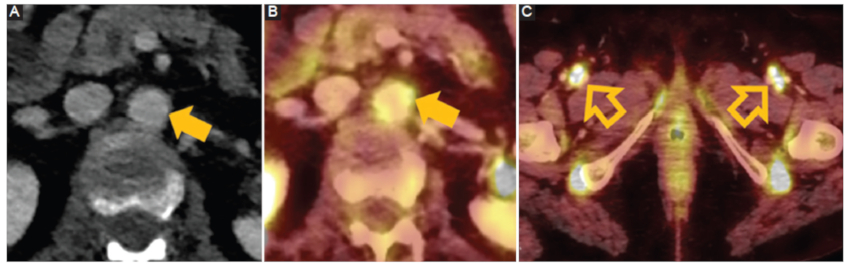

Figura 5

Arteritis de células gigantes. Hombre de 70 años. Control oncológico. TC con emisión de positrones18 fluorodesoxiglucosa A: corte axial fase porto-venosa. B: corte axial fusión. Aumento en la captación del radiotrazador en la aorta abdominal sin observar engrosamiento parietal aórtico (flecha) (SUV máx. 5,5). C: corte axial fusión. Aumento significativo en la captación del radiotrazador en las arterias femorales comunes (flecha hueca).